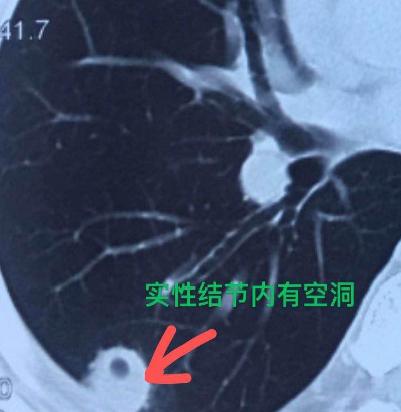

他的肺结节是怎么缩小的?这位30多岁的男性患者,一个多月前因为一直咳嗽、咳痰,吃了药也不见好,就去医院做了检查。当地医生建议他做个CT,结果发现右肺长了个结节。 这个结节一看确实让人紧张——个头不小,而且是个完全实性的。当时医生告诉他,有可能是肿瘤,小伙一听心情沉重,立刻开始多方求医,最后找到我咨询。 仔细看了CT片,我发现这个结节密度比较均匀,虽然实性,但里面藏着一个很小的小空洞,而且空洞壁很光滑。 根据我的经验,这更像是炎症引起的,就建议他先尝试抗炎治疗两周看看。 结果很让人欣慰:一个月后复查CT,那个结节明显缩小了,只剩下一点痕迹。这也证实了它确实不是肿瘤,而是一场“虚惊”——只是炎症感染引起的结节。这样一来,也避免了一次不必要的手术。 其实在临床上,我们常常会通过短期的观察或者药物试验,来帮助判断肺结节的性质。 很多朋友一查出肺结节,就特别着急,经常问我:“医生,这个结节能消掉吗?”“有没有什么药可以吃?”“听说某某药有效,我能用吗?” 我想和大家说明的是:如果结节是由急性炎症引起的,那么在炎症期及时进行抗感染治疗,结节是有可能缩小甚至消失的; 但如果结节是肿瘤性的,那一般靠药物是消不掉的。所以发现肺结节先别慌,找专业医生评估,很多时候只是有惊无险。[作揖][玫瑰]